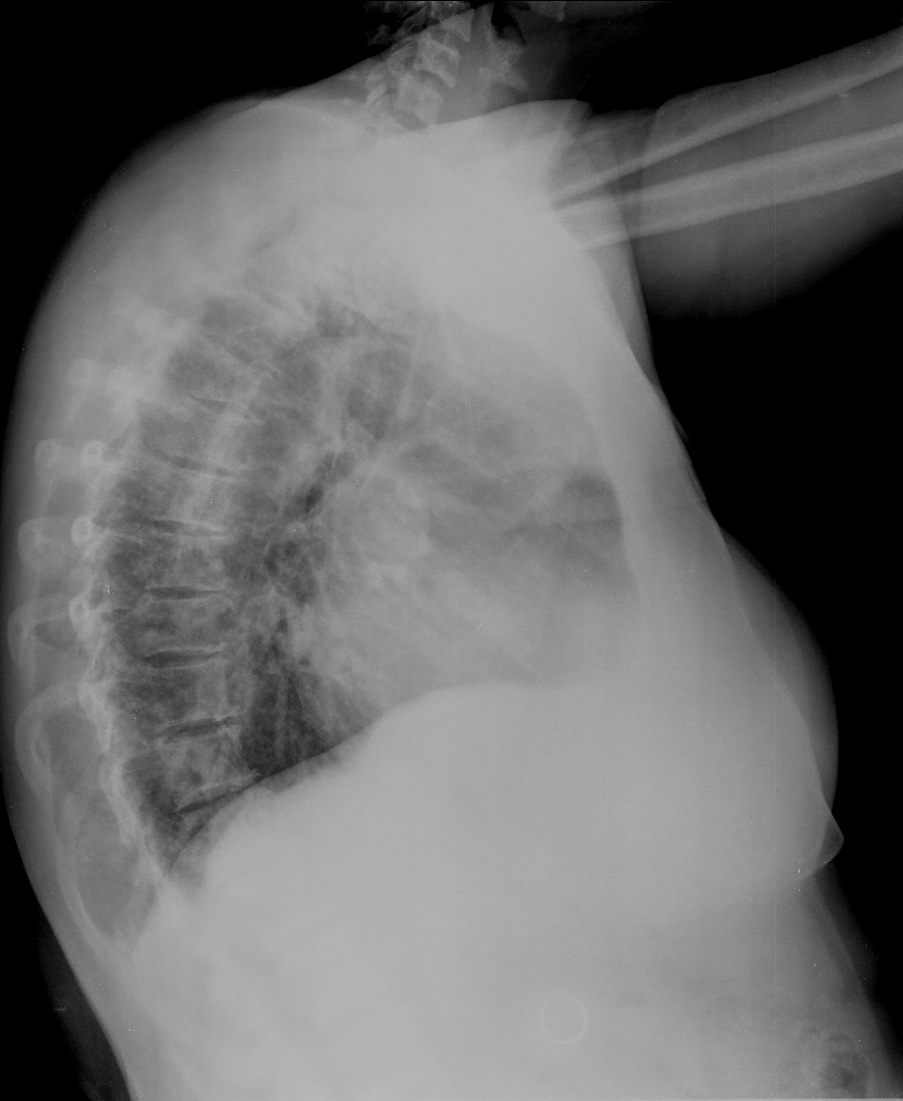

CASO: Febrícula y tos de 4 días de evolución.

Hallazgos:

- En la placa PA se observa una asimetría en los hilios pulmonares, el hilio izquierdo tiene una densidad aumentada.

- Tras examinar la placa lateral se observa un aumento de densidad en la columna que puede ser compatible con una condensación, es el signo de la desnificación vertebral.

SIGNO DE LA DENSIFICACIÓN VERTEBRAL: En la radiografía lateral normal, la densidad de la columna torácica tiende a disminuir desde la parte superior hasta el diafragma; la alteración de ese patrón por la presencia de una densidad superpuesta a la columna, indica la existencia de una consolidación pulmonar. Este signo adquiere especial valor cuando en la proyección posteroanterior la consolidación está oculta en el espacio retrocardíaco o en la base pulmonar.